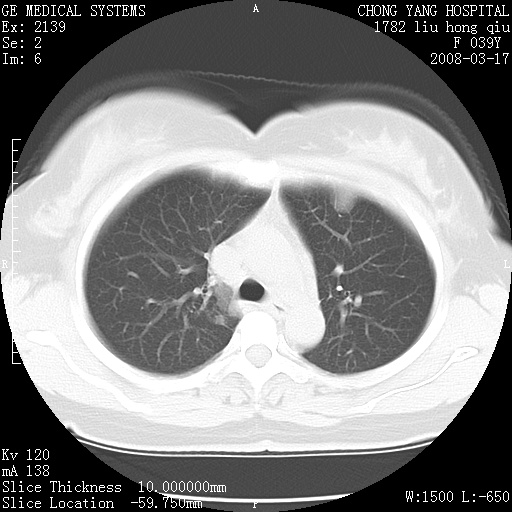

以下是引用yangxue121在2008-5-31 20:24:00的发言:[br]考虑多发胸膜间皮瘤[br]左侧少量胸腔积液[br]肝脏密度不均

以下是引用王仕学在2008-5-31 20:10:00的发言:[br]考虑胸膜间皮瘤。

以下是引用长城干红在2008-5-31 21:42:00的发言:[br]肝脏密度不均,建议增强扫描,胸膜下多发结节,考虑为胸膜来源的原发肿瘤或转移瘤。